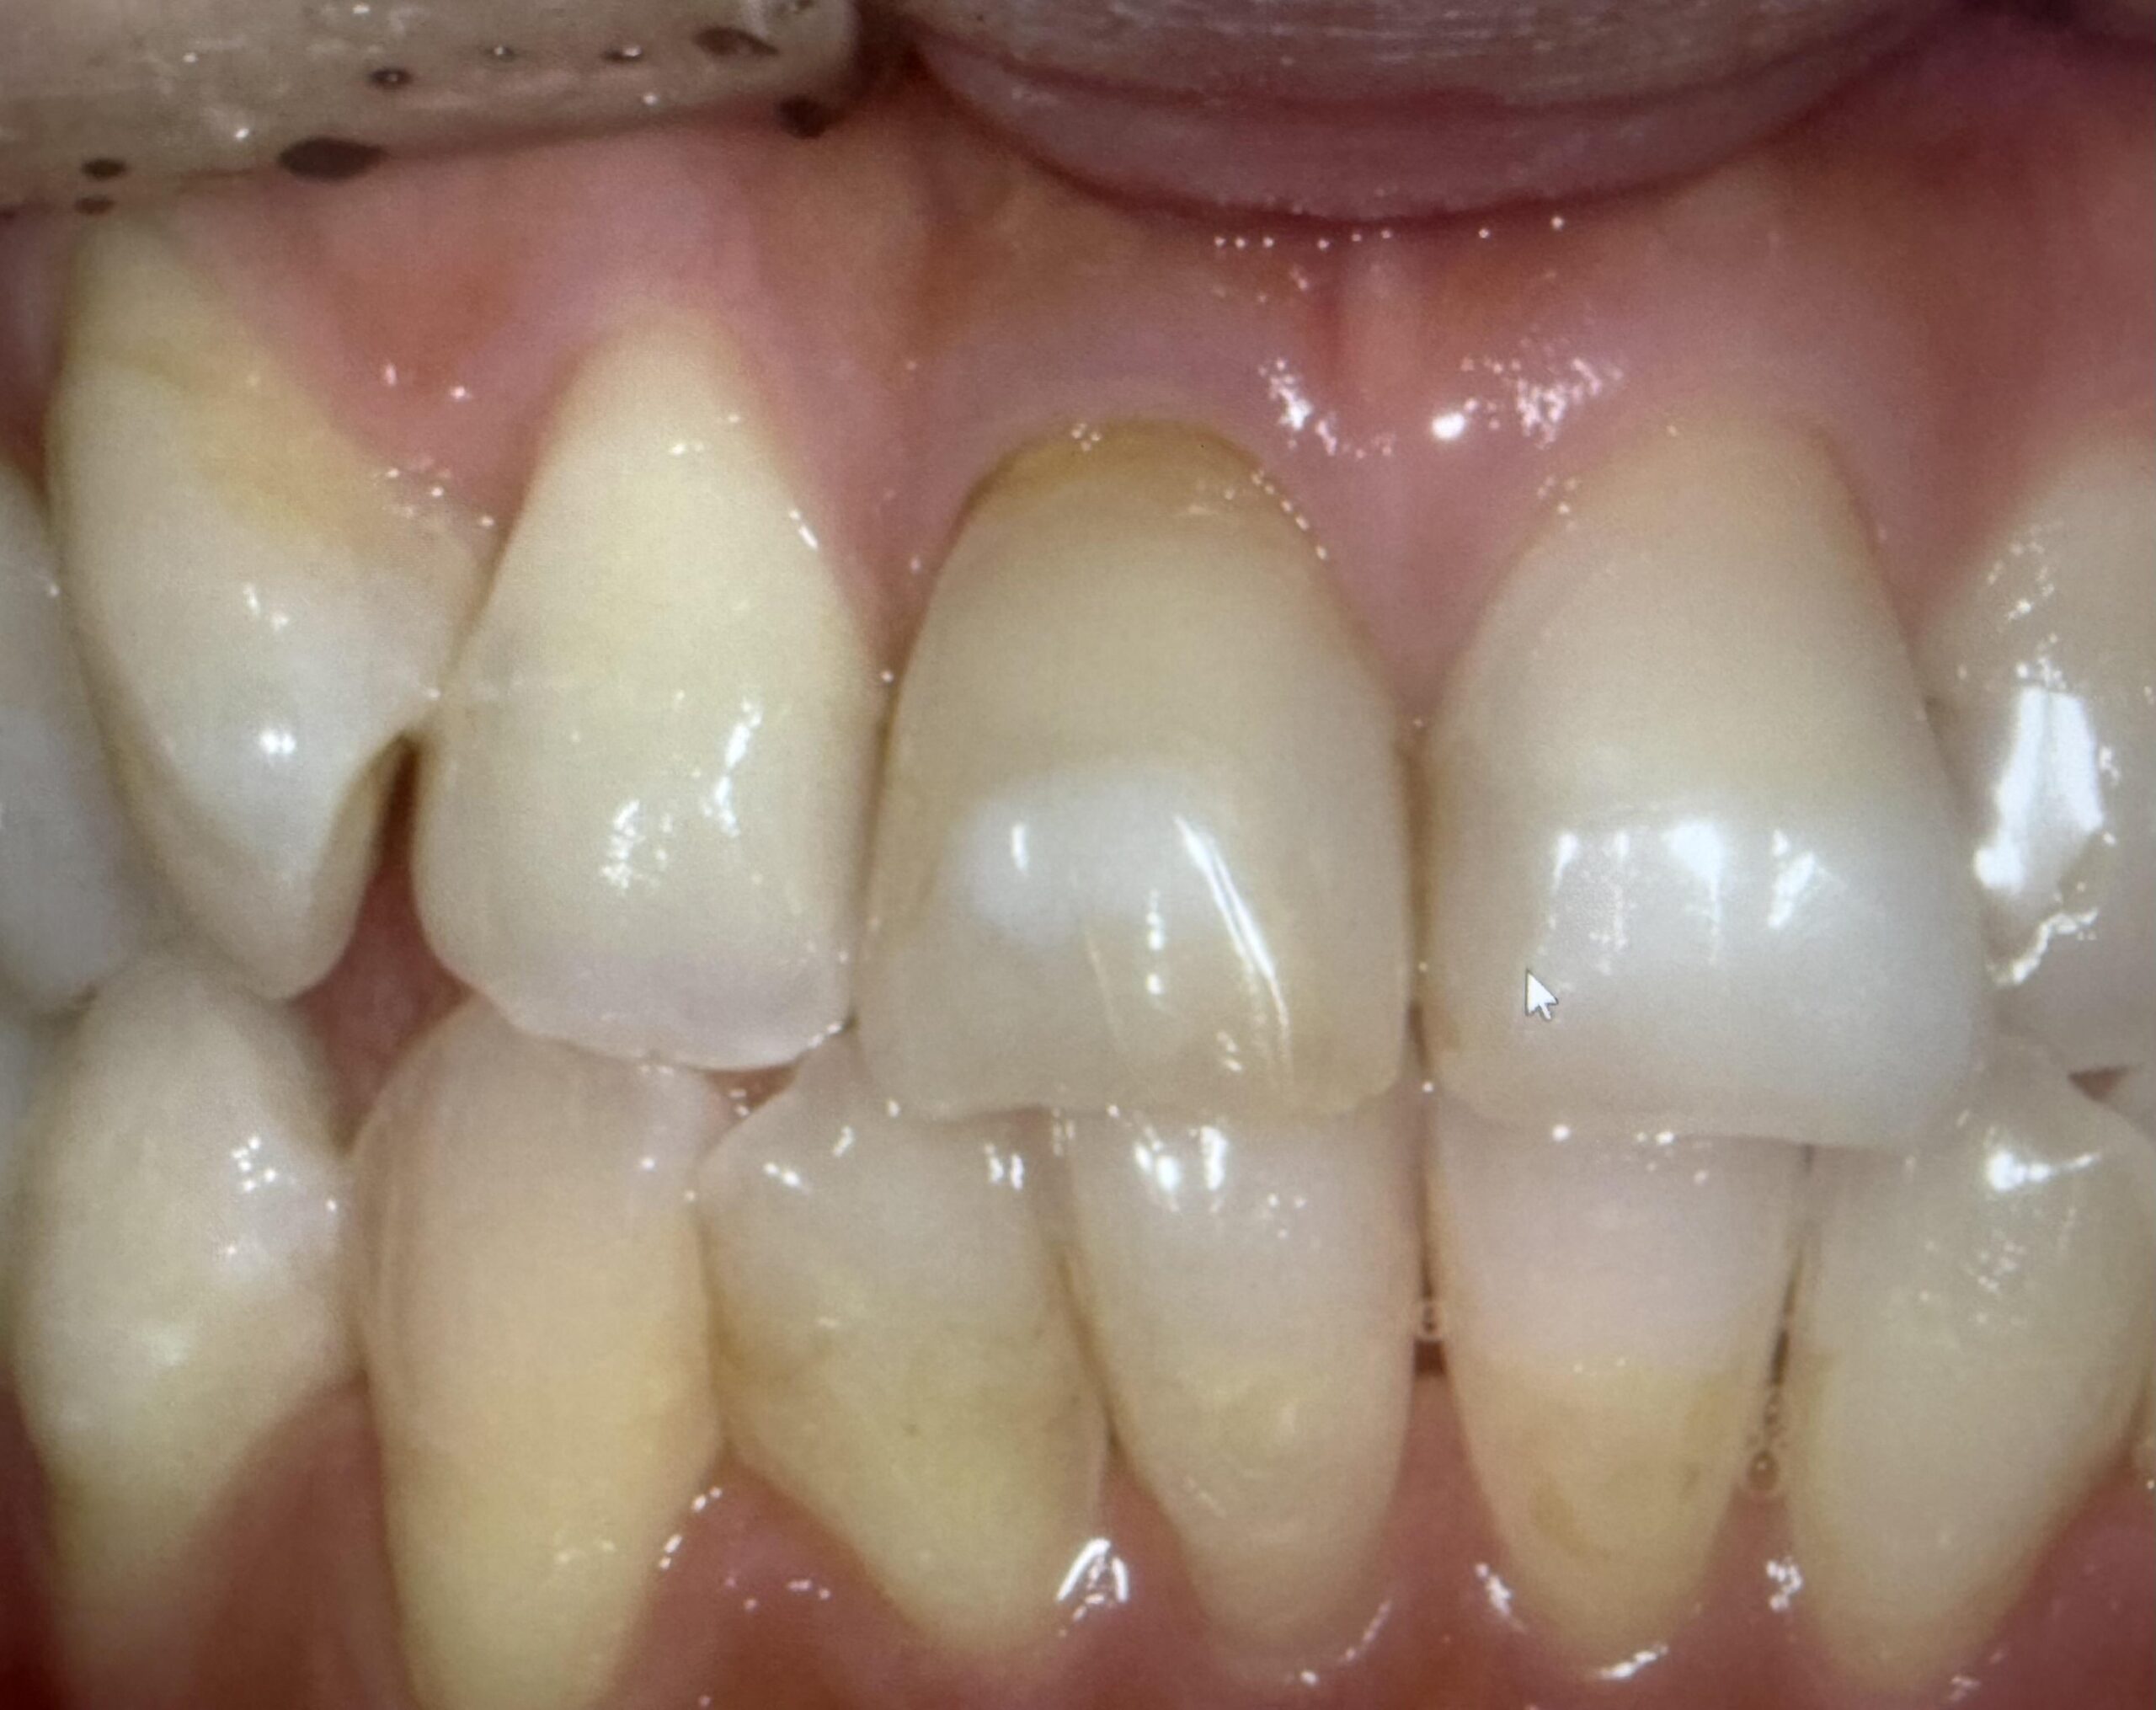

下の歯が上に上がってきている。上の歯が下に降りてきた。

それ、実はよくある現象です。結論からいうと「歯が伸びた」のではなく、噛み合う相手がいなくなって歯が動いてきた状態です。

この現象は歯科では挺出(ていしゅつ)と呼ばれます。

一番後ろの7番目の歯が抜きっぱなしになっているケースは特に多く感じます。

虫歯や、脱離で上の部分がなくなり、根っこだけが残っている場合も同様のことが言えます。